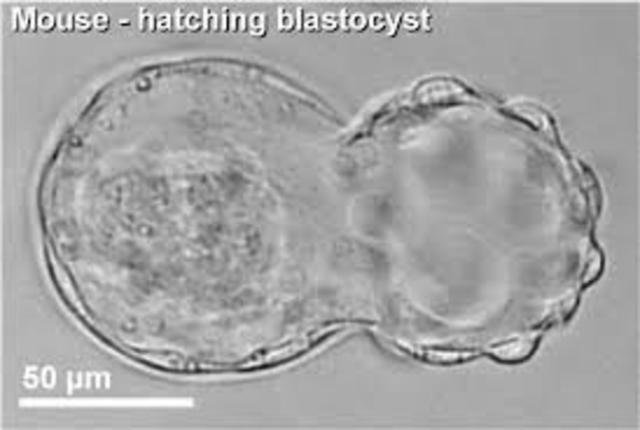

Визуально бластоциста на 5 день под микроскопом выглядит как пузырёк с жидкостью и группой клеток, которые постепенно организуются в будущие ткани.

Фотографии бластоцисты на 5 день помогают врачам и исследователям оценить качество эмбриона перед его возможной имплантацией.

Для получения точных результатов при изучении бластоцисты важно использовать высококачественные микроскопы, которые позволяют увидеть детали клеточной структуры.

Микроскопические изображения бластоцисты помогают медицинским специалистам исключить возможные аномалии и выбрать самые здоровые эмбрионы для трансплантации.

Если вы хотите лучше понять процесс развития эмбриона, фотографии бластоцисты на 5 день под микроскопом будут полезным визуальным материалом для изучения этой сложной темы.